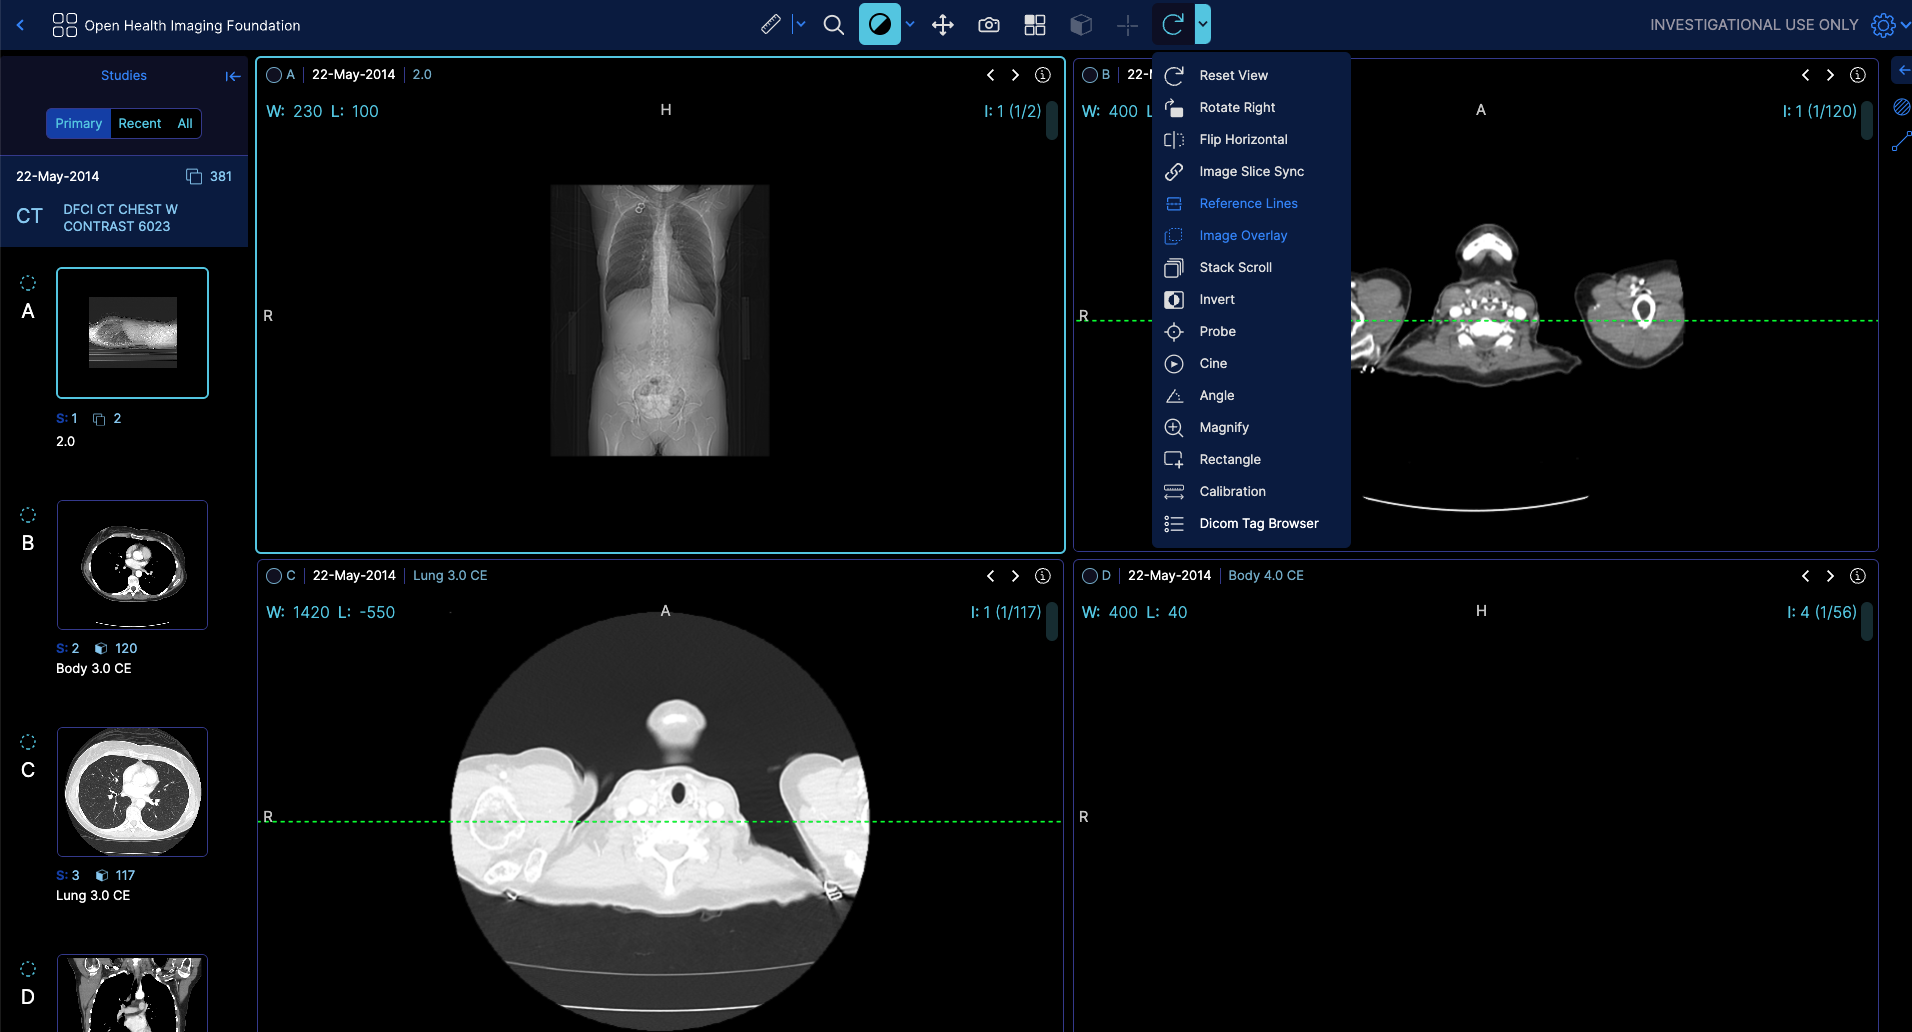

The ToolGroupService is responsible for managing tool groups in the OHIF Viewer.

It allows you to create, update, and manage tool groups and the tools associated with them. Tool groups are used to organize and control the behavior of various tools in the viewer, such as window level, pan, zoom, measurements, and annotations.